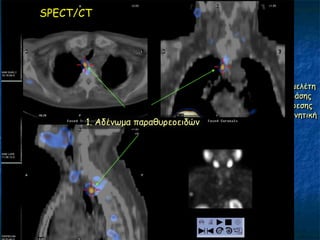

΢ύγθνηζε SPECT/CT MIBI, SPECT/CT TC99m

SPECT/CT

MIBI

1 ώνα

TC99m

(ζε άιιε μένα)

Fusion

(AMIDE)

Γπίπεδε μειέηε

δηπιήξ θάζεξ

θαη αθαίνεζεξ

πηζακά ανκεηηθή

1. Αδέκςμα παναζονεμεηδώκ

2μ αδέκςμα;

1 αδέκςμα